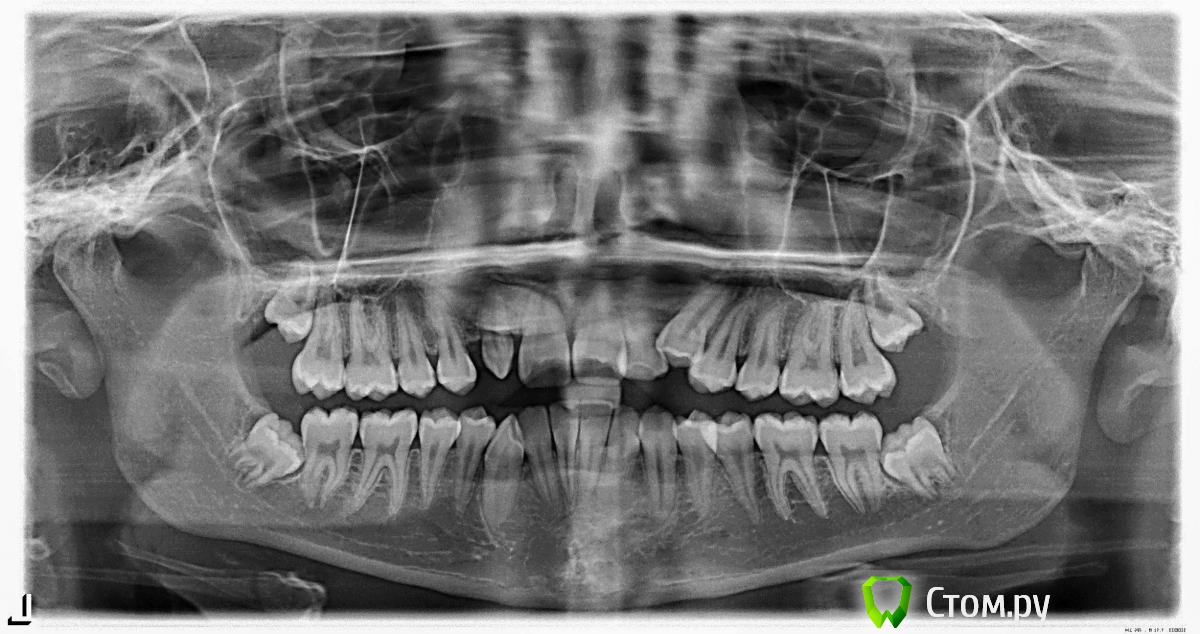

stasyaSt Опубликовано 31 марта, 2014 Автор Поделиться Опубликовано 31 марта, 2014 Фото, надеюсь подойдут Ссылка на комментарий

stasyaSt Опубликовано 30 марта, 2014 Поделиться Опубликовано 30 марта, 2014 Здраствуйте ! Моя история такова. Ношу брекеты чуть больше года. Вначале лечения было удаление всех восьмёрок. Челюсть у меня маленькая поэтому клык остался лежать в небе. Сейчас его открыли и ровняют на место.. Но. После месяца попыток вытащить зуб в линию мой врач понял, что места в кости не хватает и передние зубы едут и нужно удалять 4ку или 2ку... Т.к моя двойка от рождения шиповидная и маленькая то решили удалять её. В итоге на место 2ки и 3ки с левой стороны встанет клык, но получается асимметрия с двух сторон... Сейчас я думаю, что нужно было удалить 4ку.. Но уже поздно... Что думаете ? Встречалась ли такая история уже ? Как это будет смотреться ? Не будет ли щели ? Ссылка на комментарий